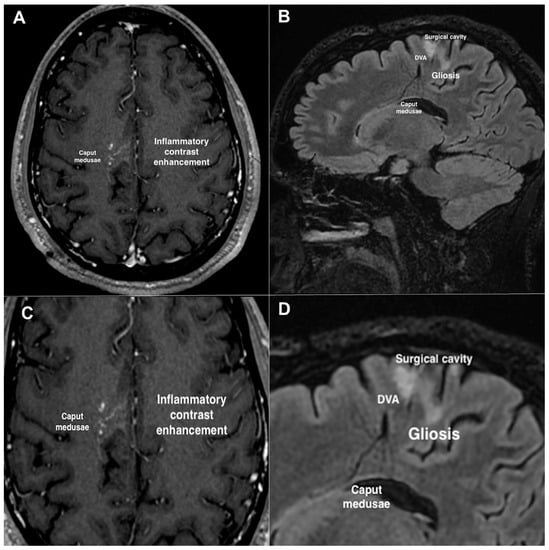

2. Case Description